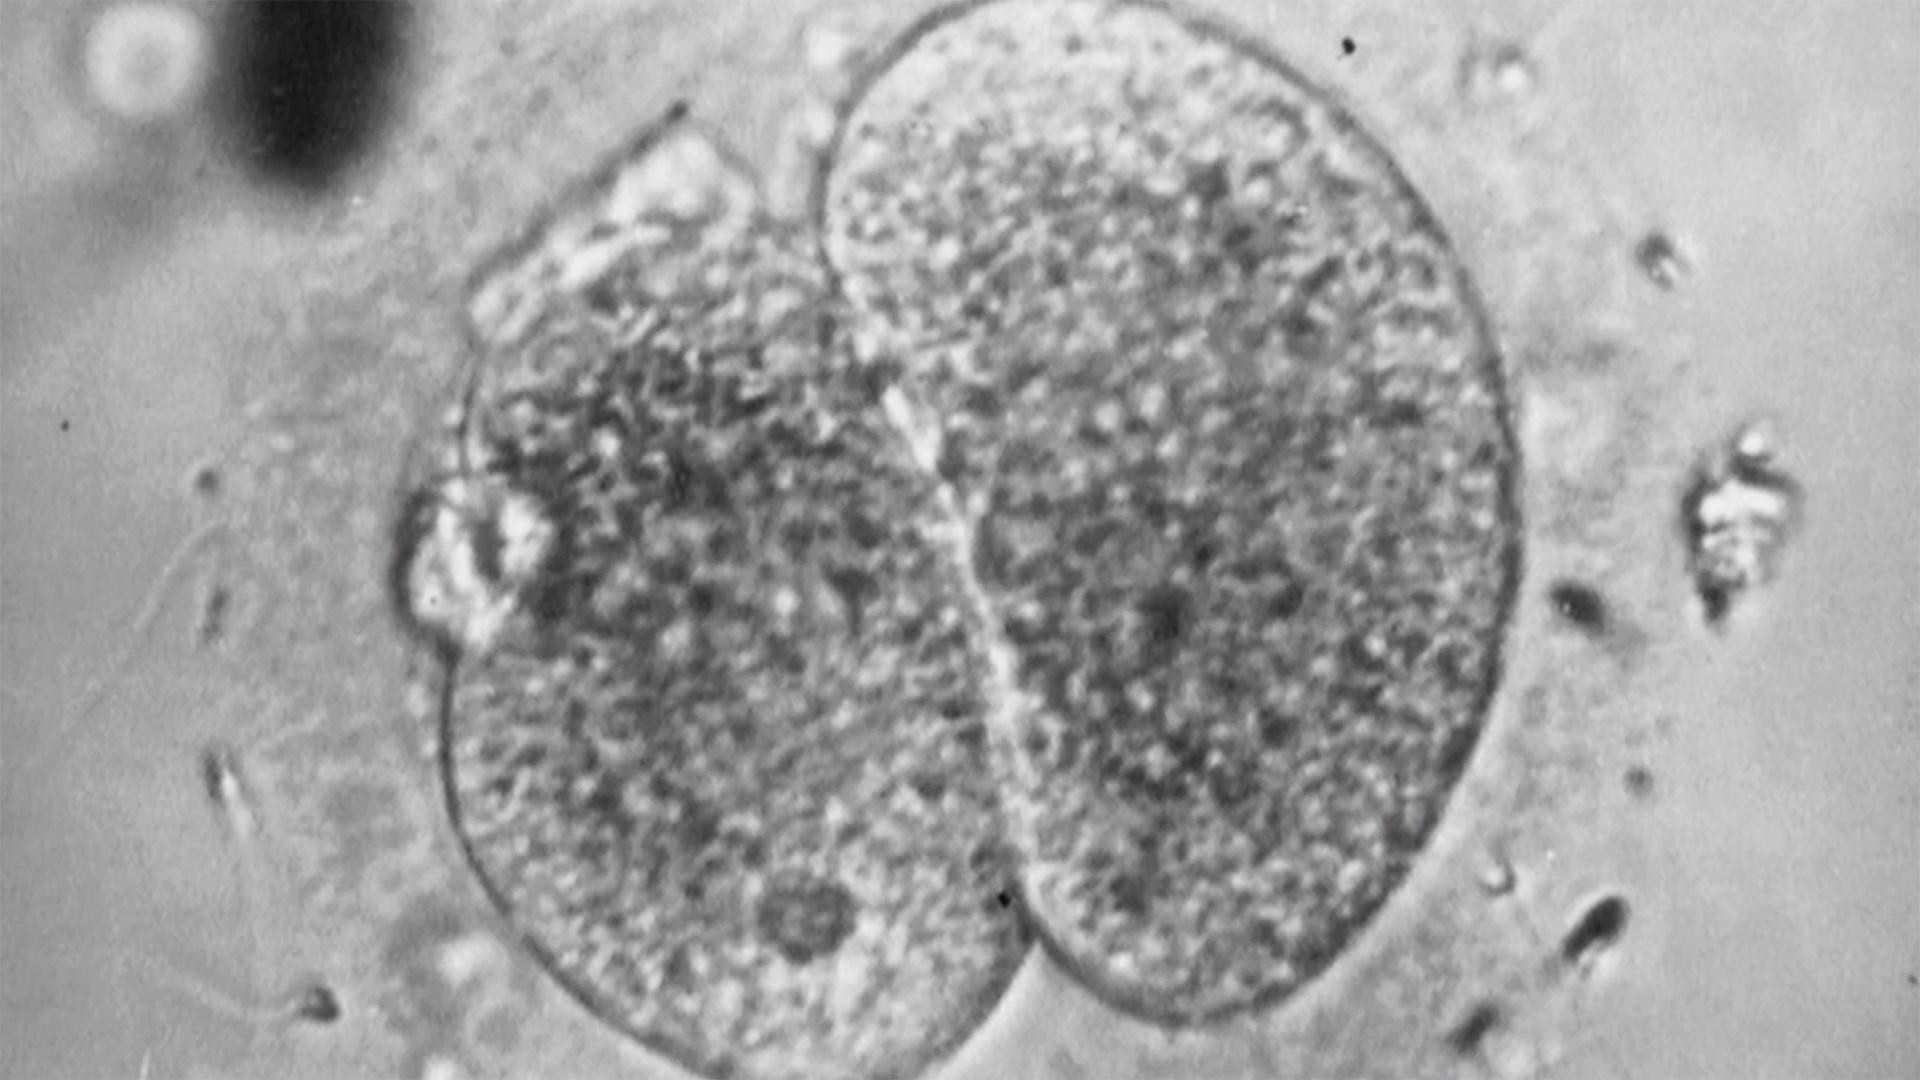

The world's first successful in-vitro fertilization takes place in Great Britain resulting in a live birth on July 25,1978.